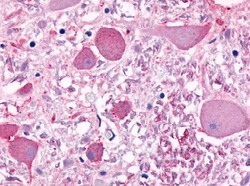

- Main image

- Experimental details

- SP4091P CELSR1 antibody staining of Formalin-Fixed, Paraffin-Embedded Human Brain.